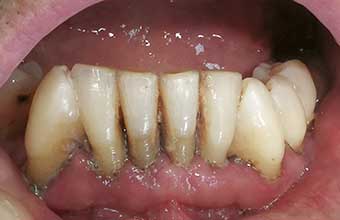

A periodontite agressiva juvenil é uma doença gengival séria que afeta jovens. Ela causa destruição rápida do osso e dos tecidos que sustentam os dentes. O diagnóstico precoce é crucial para evitar a perda dentária.

A periodontite agressiva juvenil, quando não tratada, pode trazer sérias consequências para a saúde bucal. Por isso, a limpeza profissional não é só um cuidado estético, é a base para o controle dessa condição. Dentistas e higienistas têm as ferramentas e o conhecimento para remover aquela placa bacteriana e o tártaro que o dia a dia em casa não alcança. É um passo fundamental para frear a progressão da doença.

Nesse tratamento, o foco é a remoção minuciosa das bactérias. Os profissionais utilizam instrumentos específicos para limpar profundamente as bolsas periodontais, que são aquelas espaços que se formam entre o dente e a gengiva quando a doença avança. O objetivo é criar um ambiente bucal mais saudável, onde a gengiva possa começar a se recuperar e a inflamação diminua. É um trabalho delicado, que exige precisão.

Se você ou alguém que você conhece está lidando com periodontite agressiva juvenil, saiba que existem caminhos eficazes para o tratamento. A primeira linha de ataque geralmente envolve procedimentos feitos no consultório do dentista. São eles que vão limpar profundamente as bolsas periodontais, removendo o máximo possível da bactéria que causa o problema. Isso é crucial para frear a progressão da doença.

A regeneração tecidual entra em cena depois que a inflamação está sob controle. O objetivo é recuperar os tecidos que foram danificados pela doença. Isso pode envolver procedimentos como raspagem e alisamento radicular para limpar as bolsas periodontais. Em casos mais avançados, a gente pode pensar em enxertos ósseos ou de gengiva, tudo para ajudar o corpo a se reconstruir.

Vamos falar sério agora sobre periodontite agressiva juvenil. Se você ou alguém que você conhece está lidando com isso, sabe que é um assunto delicado. Basicamente, quando a doença periodontal avança e a inflamação já causou perdas ósseas significativas, a cirurgia pode ser o caminho. É aquela situação em que a limpeza profunda que fazemos não consegue mais alcançar as bactérias mais problemáticas.

Eu já vi casos onde a gengiva se retrai muito, deixando a raiz do dente exposta. Isso não é só questão estética, viu? Aumenta a sensibilidade e o risco de cáries nessa área. A cirurgia periodontal entra para tentar recuperar o suporte dos dentes, removendo as bolsas periodontais e, em alguns casos, até regenerando o osso perdido. É um procedimento para quando outras abordagens não foram suficientes, entende?